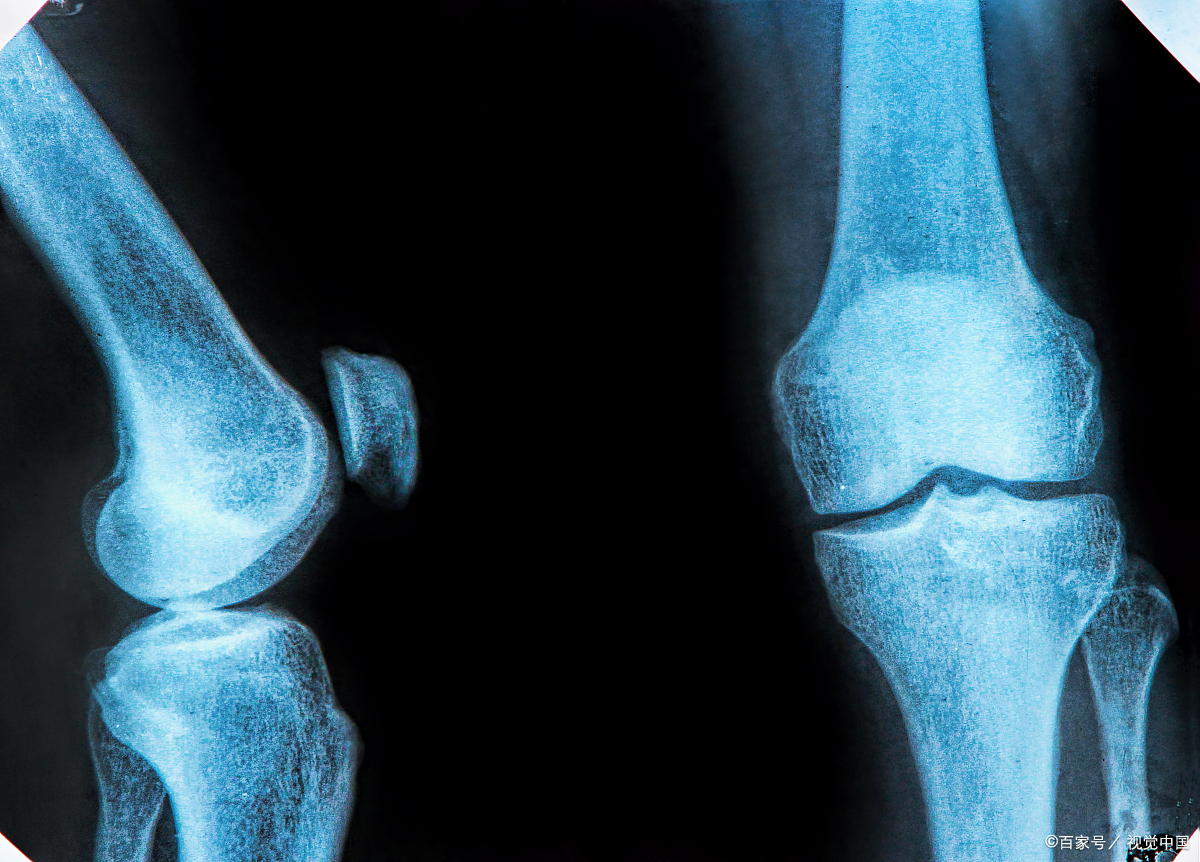

当然,这并不是绝对的,孩子最终能长多高取决于骨骺线是否闭合。骨骺线是指骨干与骨骺之间的软骨,软骨在x光片上显示为透明带。

随着年龄的增长,软骨会继续骨化,最终成为x光片上的紧密缝。此时,这意味着儿童的骨骺线已经闭合,骨骼基本停止生长,不会继续生长。

因此,男孩变声后, 家长应立即进行骨龄检查,估计生长余量, 骨龄是骨骼的年龄,也是人体骨骼发育的重要指标,代表着孩子的真正发育水平。